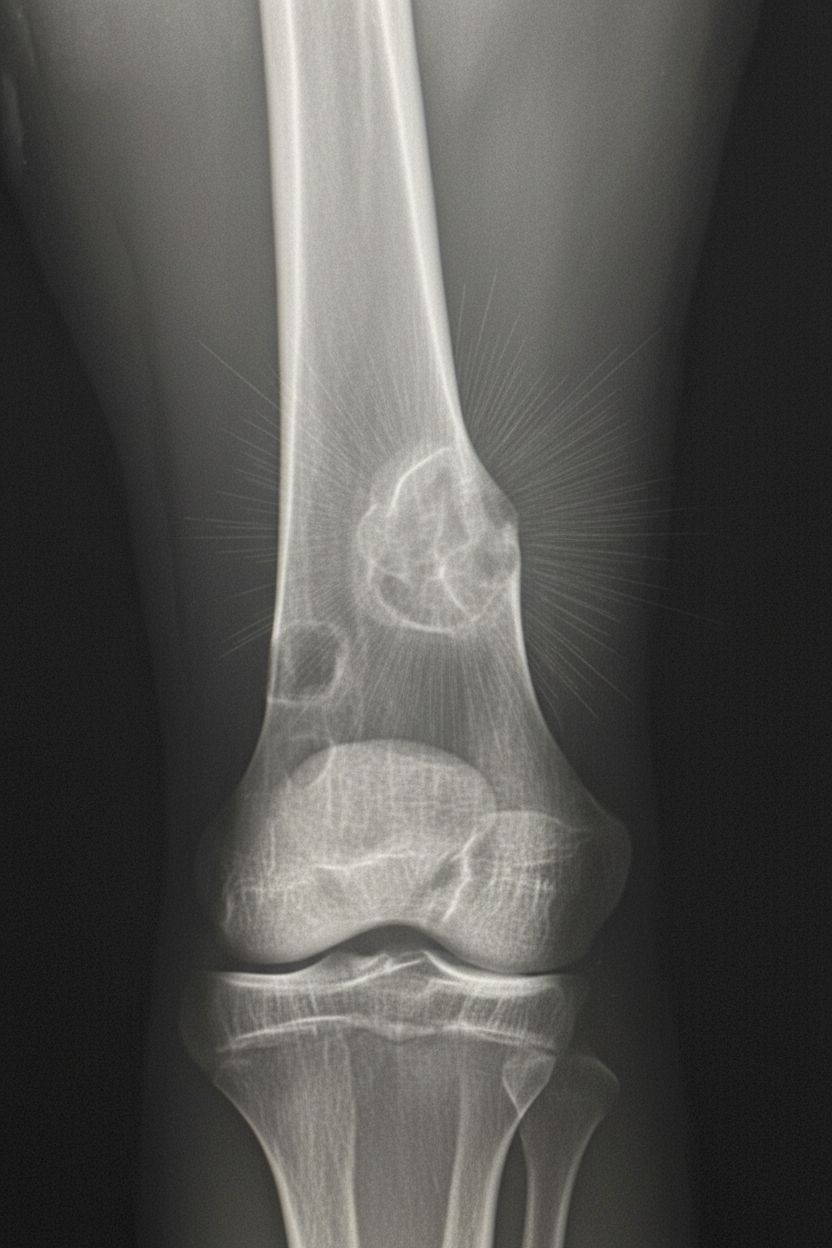

- Osteosarcoma: Most common primary malignant bone tumor (excluding myeloma). Ages 10-20. Metaphysis of long bones. X-ray: Codman's triangle, sunburst pattern.

- Osteosarcoma: Shows Codman's triangle and a sunburst pattern in the metaphysis.